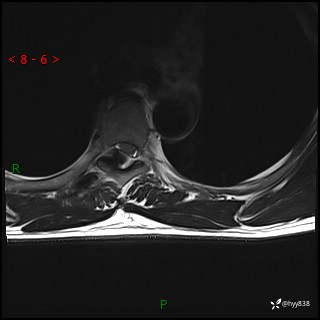

axi T2WI